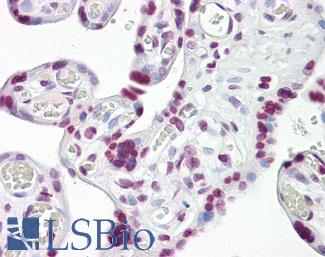

TP53

Anti-p53 antibody IHC of human placenta. Immunohistochemistry of formalin-fixed, paraffin-embedded tissue after heat-induced antigen retrieval. Antibody LS-B7722 dilution 10 ug/ml.